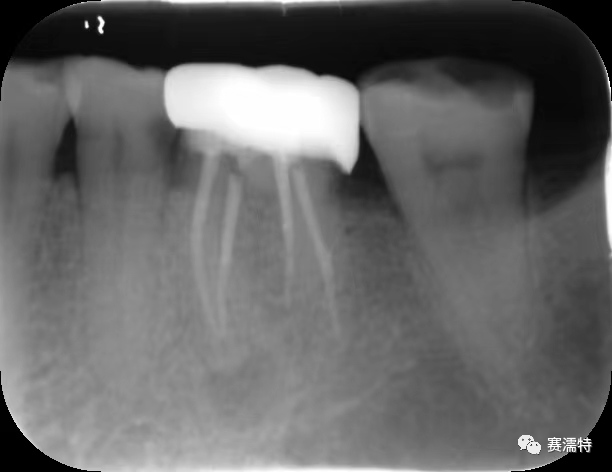

C-Root SP是預混合的、可即刻應用的、可注射的、遇水凝固的硅酸鹽類生物活性陶瓷糊劑材料,主要成分為硅酸鍶、氧化鋯、磷酸鈣、氫氧化鈣,用于根管的密封和永久充填,適合單尖法、側壓法和熱牙膠法。 C-Root SP為世界口腔醫生提供一個“鍶生物陶瓷”的新選擇! >>>